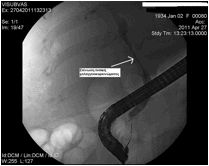

Η ERCP συνήθως διενεργείται σε ασθενείς με γνωστή χοληδοχολιθίαση ή σε εκείνους τους ασθενείς στους οποίους υπάρχει τουλάχιστον μέτρια κλινική υποψία χοληδοχολιθίασης. Στους ασθενείς με χαμηλή κλινική υποψία χοληδοχολιθίασης, προτιμώνται άλλες διαγνωστικές εξετάσεις όπως η MRCP και ο ενδοσκοπικός υπέρηχος, για την ελαχιστοποίηση της πιθανότητας επιπλοκών. Η συνήθης μέθοδος για την απομάκρυνση των λίθων είναι ηενδοσκοπική σφιγκτηροτομή, η οποία επιτρέπει την διάνοιξη του φύματος και την εξαγωγή των λίθων με τη χρήση μπαλονιού ή καλαθιού (basket) προς το δωδεκαδάκτυλο. Εικόνες 1 και 2.

Eικόνα 1: Ασθενής με εναπομείναντα ευμεγέθη           Εικόνα 2:Ασθενής με λιθίαση στη μεσότητα του

λίθο (μαύρο βέλος) στο κατώτερο τμήμα του                           χοληδόχου πόρου (κόκκινο βέλος), καθώς και

χοληδόχου πόρου, μετά από χολοκυστεκτομή –          ευμεγέθη λίθο στον αυχένα της χοληδόχου κύστης

Αφαίρεση με μπαλόνι (λευκό βέλος).                      (μπλε βέλος). Έγινε σφιγκτηροτομή και καθαρισμός του πόρου και την επόμενη ημέρα ο ασθενής υπεβλήθη σε λαπαροσκοπική

χολοκυστεκτομή.